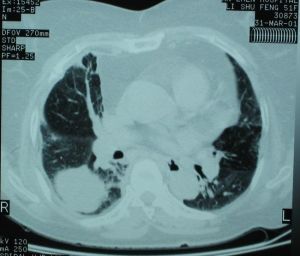

2.CT檢查

球形病灶以中低密度陰影為多,多數病灶邊緣模糊,無分葉及毛刺征;肺門淋巴結也不腫大;體層攝影顯示病灶輪廓不清。多數患者病灶周圍及肺門方向有較長索狀陰影,及所謂“局部充血徵象”提示腫塊為炎症。